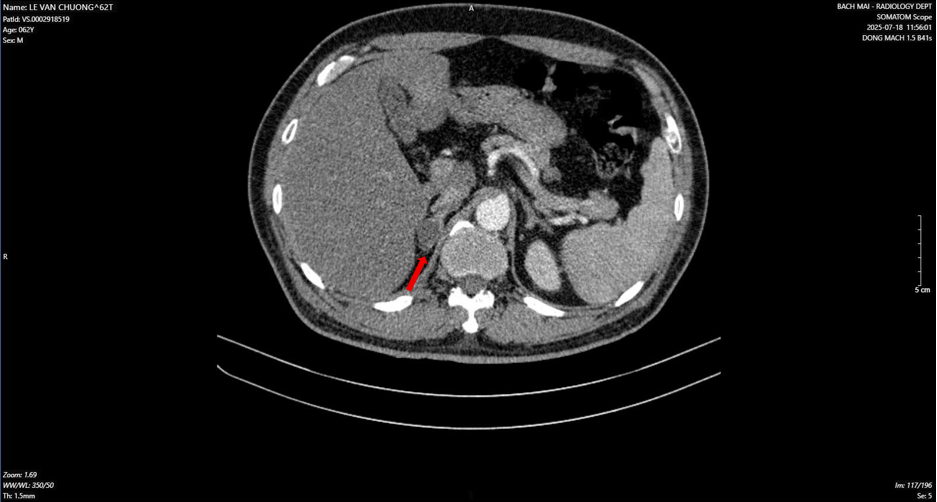

Hình ảnh dày tuyến thượng thận phải tạo nốt có kích thước 19 x 17 mm (mũi tên đỏ) - Ảnh BVCC